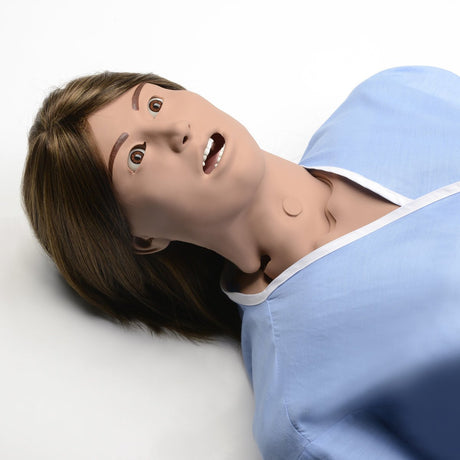

Head and Neck

Head and Neck